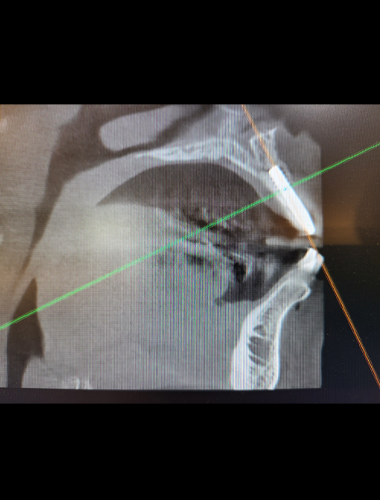

インプラントを埋入するためには、ドリルで顎の骨に穴を明ける必要があります。シムプラントガイドシステムとは、インプラントを正確な位置に埋入するためのガイドシステムです。

事前にコンピュータ上で手術をシミュレートし、そのデータに基づいて「サージカルガイド」と呼ばれる手術用の装置を作成します。サージカルガイドとは、手術に使用するドリルなどが接続できるマウスピースのような形の装置です。このサージカルガイドを口にはめてドリルを接続すると、事前にシュミレートした通りの位置、方向を正確にガイドする事ができます。これにより、より安心・安全なインプラント治療を実現する事が可能です。